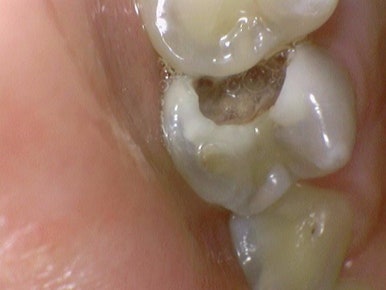

치료 전, 치료 중간 신경치료해야 할 만큼 깊은 충치를 보여드리기 위해 찍은 사진

저희 연세 예 감 치과는 다수의 구강카메라를 보유하여

치료해야 하는 치아의 이유를 환자분께 빠르게 직접 보여드리고 기록합니다.

필요한 경우에는 치료 중간중간 바로바로 구강카메라로 찍어서

깊은 충치를 보여드립니다.

충치치료, 레진, 크라운, 인레이, 발치 등 왜 그 치료를 해야하는지

과잉진료없이 객관적인 근거를 보여드립니다.